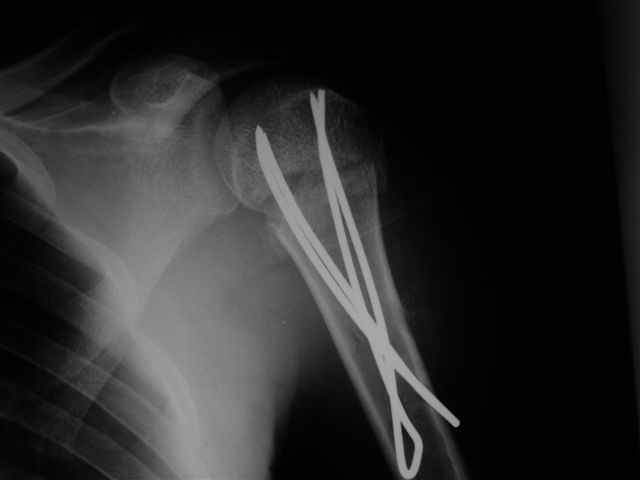

Re: Перелом шейки плеча

Спасибо за участие в дискуссии -перелом шейки плеча, для себя я прояснил многие технические моменты...

Посылаю послеоперационные Рг граммы.